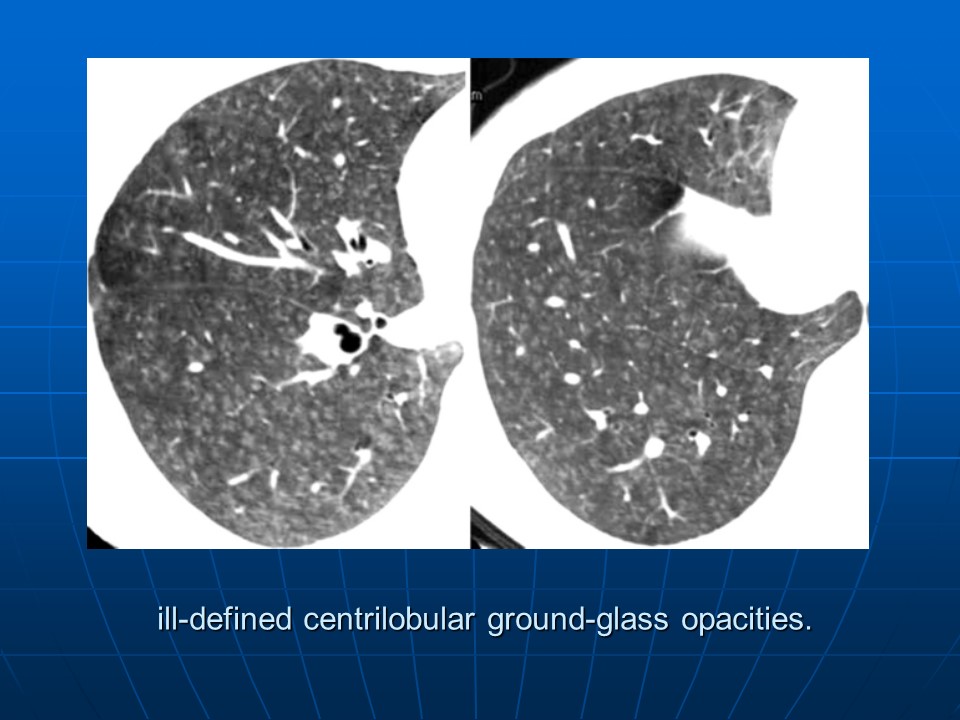

HRCT树芽征的诊断价值